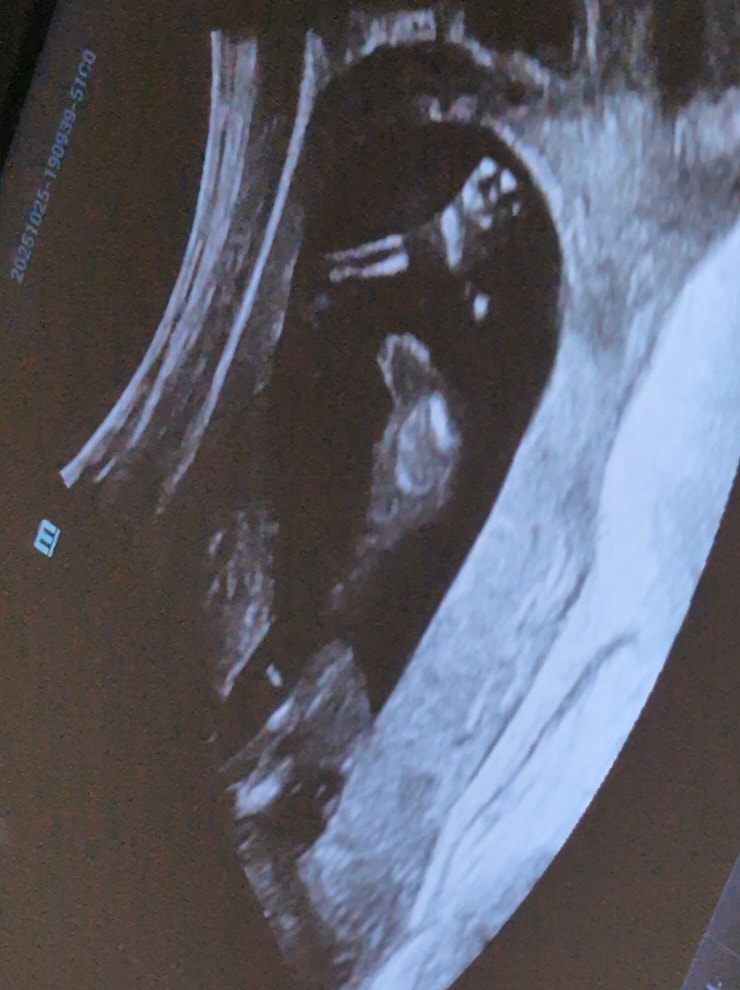

УЗИ, КТГ, доплерКрошечные лапки поприветствовали с самого начала узи. Отплясываем ногами знатно) Шустрый, шустрый сын🤭

15+1, время летит. Идем дальше 💙